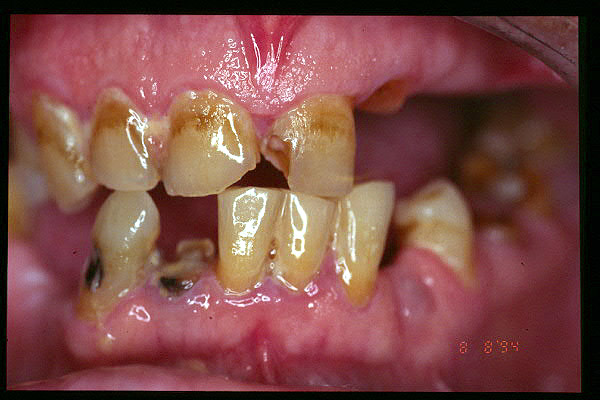

CM Caries, patología periodontal, desgaste.